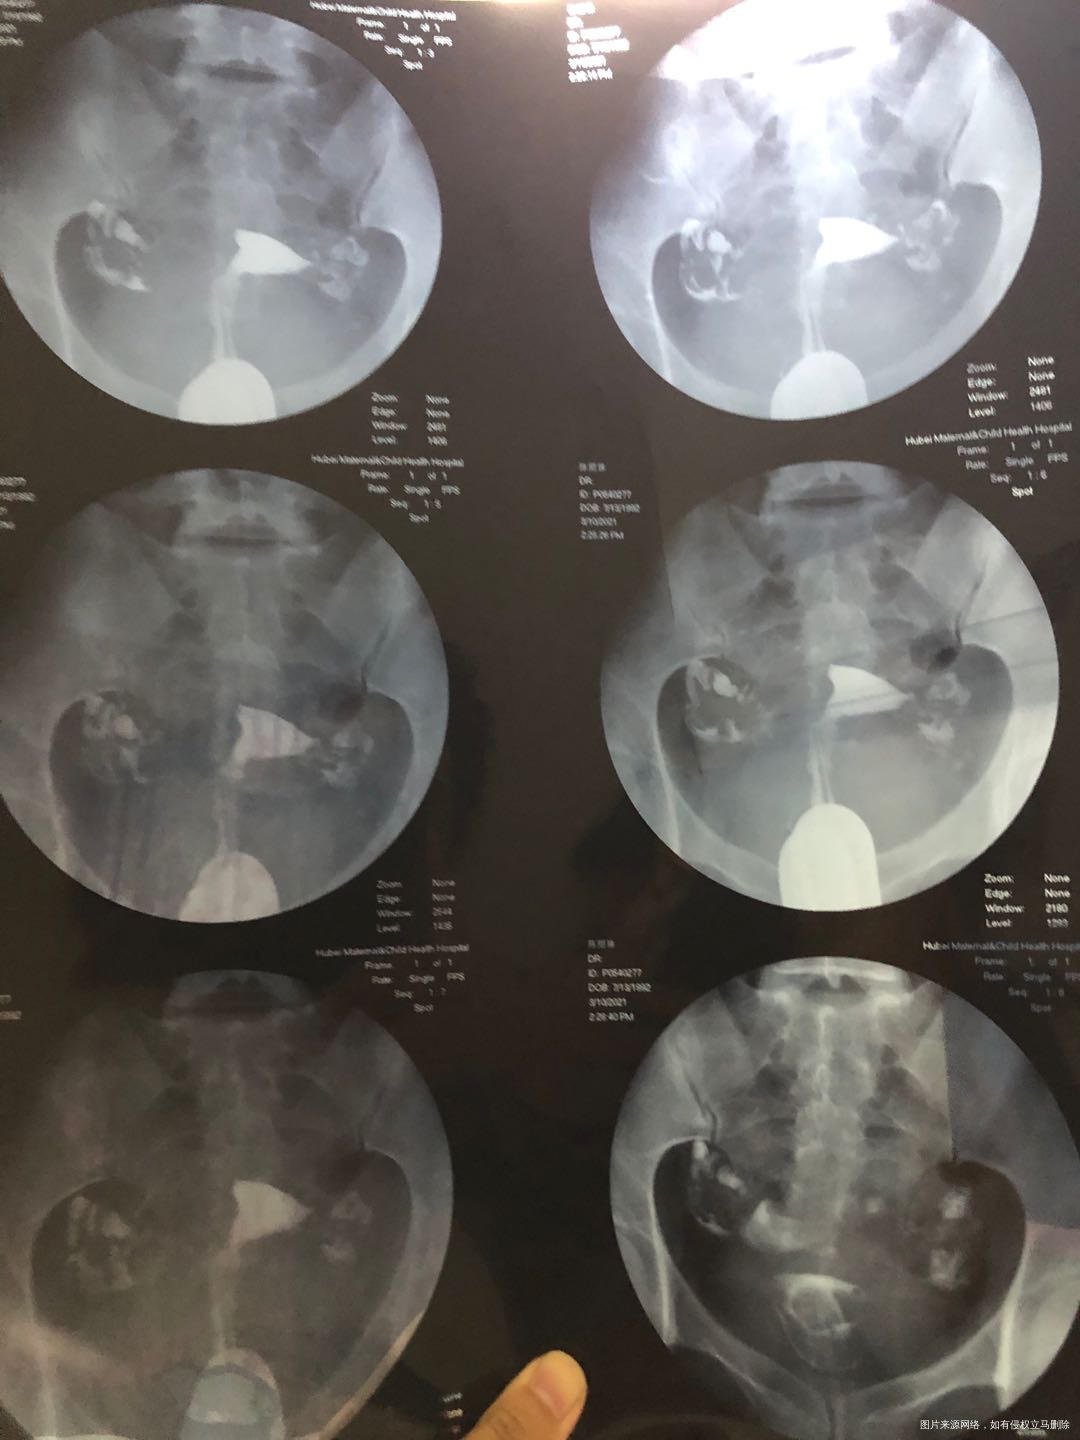

21年3月10日,例假干净后四天造影,结果双侧通而不畅,如图。